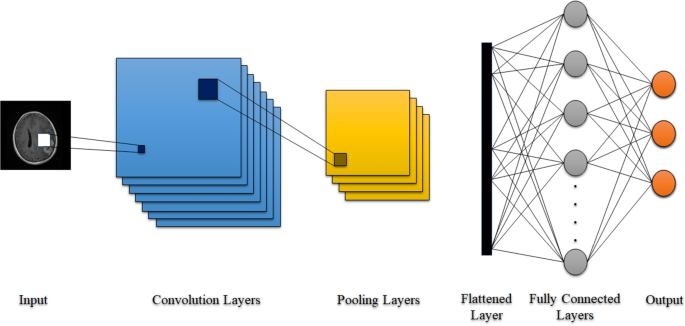

Sophisticated imaging techniques can pinpoint brain tumors. Diagnostic tools include computed tomography (CT or CAT scan) and magnetic resonance imaging (MRI) . Other MRI sequences can help the surgeon plan the resection of the tumor based on the location of the normal nerve pathways of the brain. Intraoperative MRI also is used during surgery to guide tissue biopsies and tumor removal. Magnetic resonance spectroscopy (MRS) is used to examine the tumor's chemical profile and determine the nature of the lesions seen on the MRI. Positron emission tomography (PET scan) can help detect recurring brain tumors.